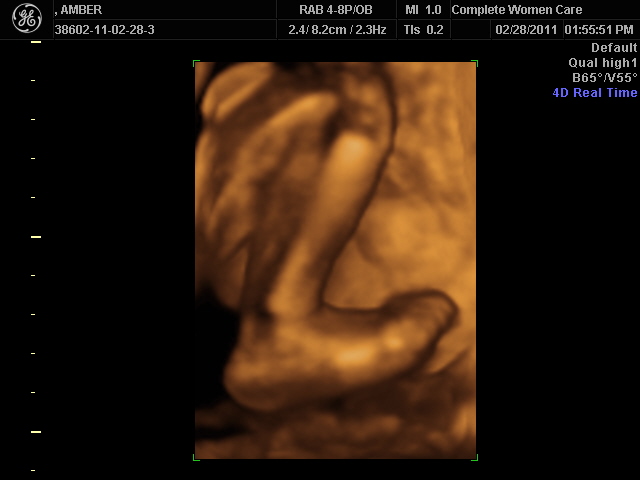

It's been a while since I last wrote.. we've been busy! I simply cannot believe how fast this pregnancy has gone by. I'm very excited to meet my son and back at the end of February we got to take a peek into my belly to see him.  It was really fun.  Some of the family joined us at the doctor's office to have a look at August, including my little Teagan.  He was very cooperative during the ultrasound and we got some great pictures!  The best part, for me, was seeing Teagan's reaction to the whole thing.  She was so cute!  Everytime that Teagan spoke to him, he would turn and open his eyes!! It seems that he already loves his big sister :)  Here are some pics from the ultrasound:

He has his hand up against his face and is sleeping here!

Here is his leg and foot (resting against my rib!!)